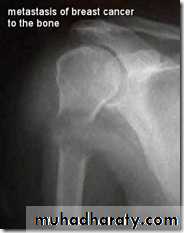

(3) Blood streams: it is by this route skeletal metastases occur. In order of the frequency the lumbar vertebrae, femur, thoracic vertebrae, rib and skull are affected and these deposits are generally osteolytic. Metastases may also commonly occur in the liver, lung, brain, and occasionally adrenal glands and ovaries.